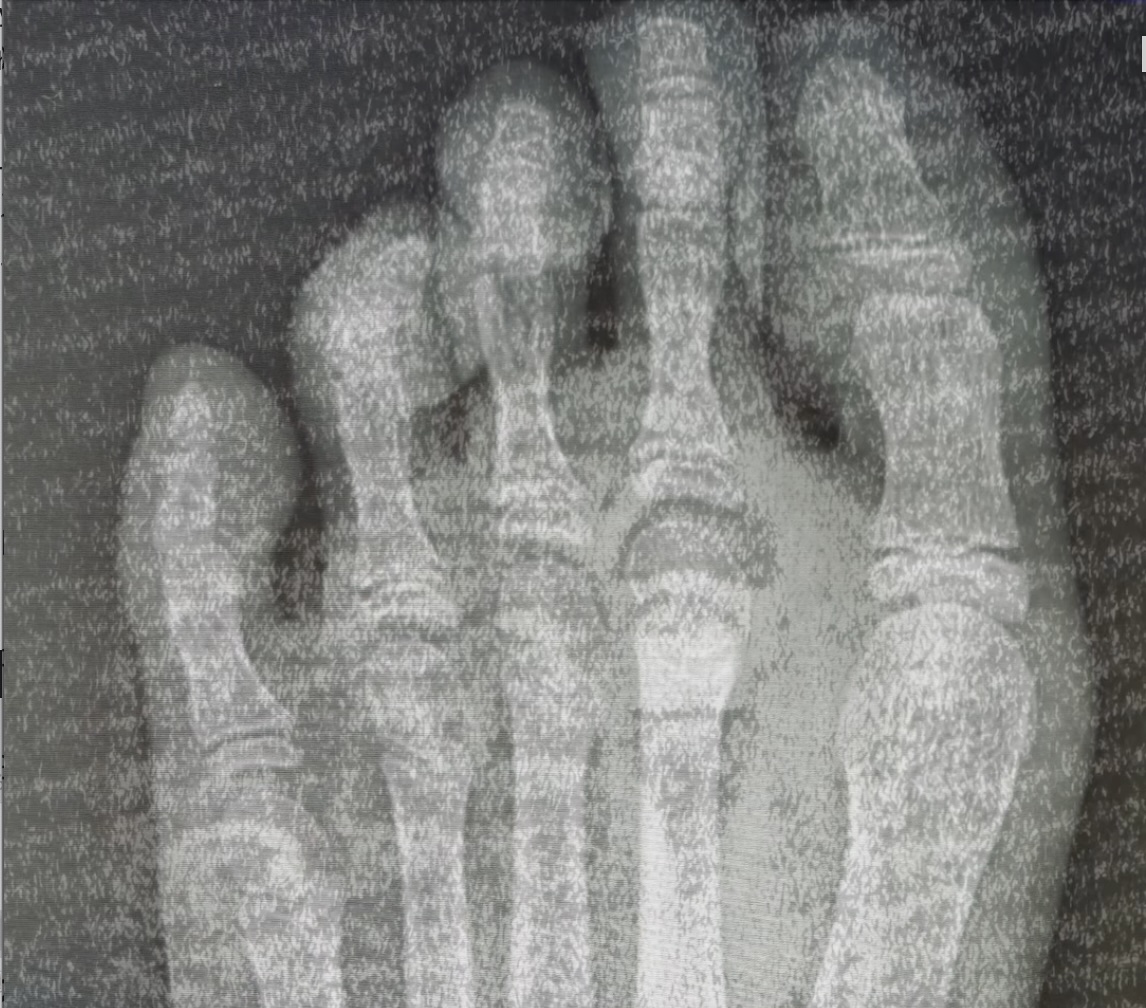

突然の試練

自主練中、足に激痛。診断は「骨挫傷」。

ずっと準備してきたソロ演舞は、断念せざるを得なかった。

悔しくて、涙が止まらなかった。

怪我(骨挫傷)で練習ができない日々の記録